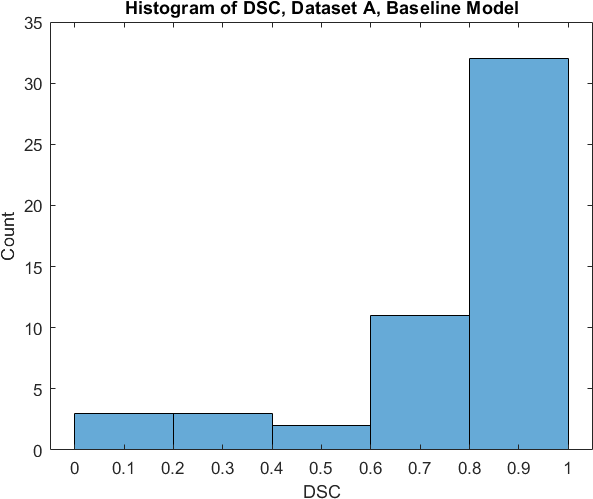

Qualitative prediction results of the two proposed models (baseline nnU-Net and nnU-Net with coordinate convolutions) on the two datasets are shown in Figure 2. Tables 1 and 2 summarise the quantitative performances in terms of DSC and area statistics. Histograms of the DSC values are shown in Figure 3. The median DSCs between the manual segmentations on the subsets of 10 images (i.e. the estimates of inter-observer variability) are also shown in Table 1.

It can be seen that, despite having fewer images, the baseline model for Dataset A obtained a higher median DSC than the model for Dataset B. For Dataset A the coordinate convolution model improved the DSC and reduced the area error and bias. In two-tailed Wilcoxon signed rank tests (0.05 significance) the difference between the baseline DSC and that of the coordinate convolution model was found to be statistically significant for Dataset A () but there was no statistically significant difference for Dataset B (). Interestingly, for both Dataset A and Dataset B, both the baseline and coordinate convolution models performed better than the estimate of inter-observer variability. However, we note that the inter-observer variability is quite high (i.e. median DSCs of 0.78 and 0.71), likely reflecting the difficulty and partly subjective nature of the effusion segmentation task. Therefore, it seems likely that the deep learning models are learning to segment effusion in the style of the main observer, which may not always be consistent with the second observer. In addition, the histograms shown in Figure 3 suggest that there are a significant number of failure cases in the outputs of both models (although fewer for the coordinate convolution model for Dataset A), again reflecting the difficulty of the task.